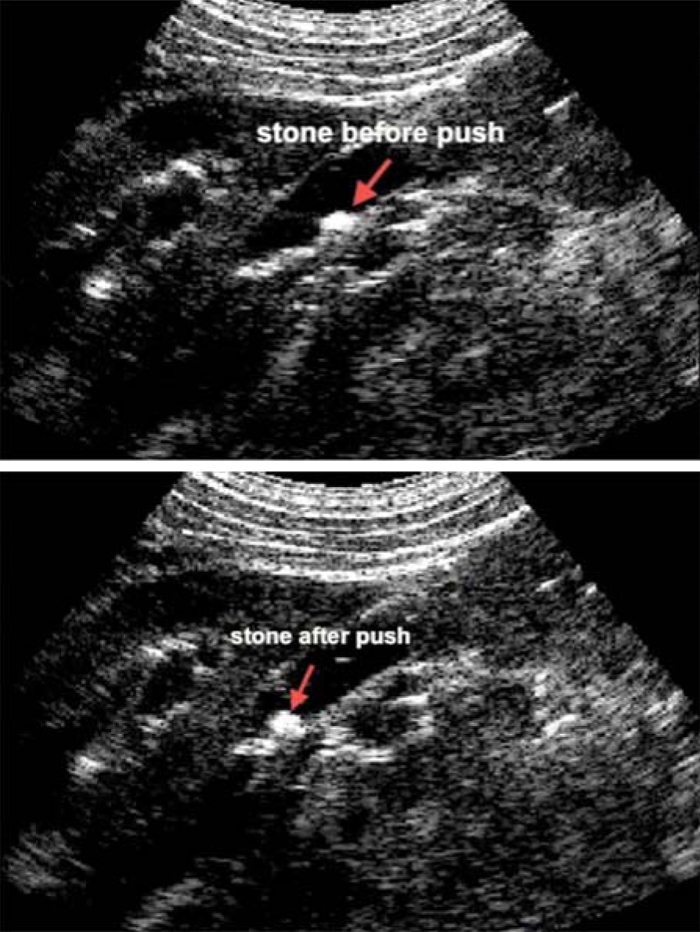

Kidney Stones Ultrasound